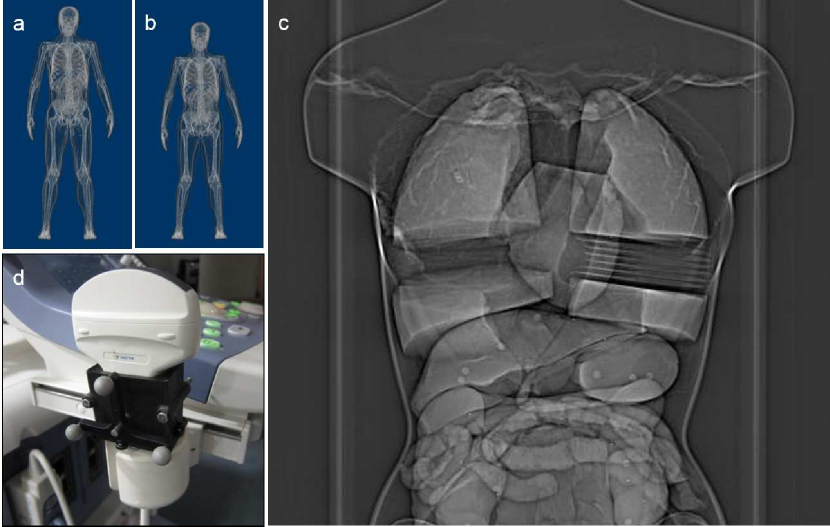

2.3.1 Digital Livers

XCAT is a digital whole body phantom with detailed, high-resolution and dynamic tissues [Segars et al., 2010] as shown in Fig. 2a and Fig. 2b. In this paper, the isotropic resolution of the volume was set at 0.625mm0.625𝑚𝑚0.625mm. 21 time frames were collected between exhalation and inhalation. 3D meshes of two XCAT livers (one male and one female) were segmented and processed with Analyze (AnalyzeDirect, Inc, Overland Park, KS, USA) and MeshLab [Cignoni et al., 2008]. A 3D SSM was constructed for each digital liver.

The optimal scan plane for each liver was determined with approximately 200200200 informative vertices and was used to slice the meshes in the 3D SSM. The intersection contours were projected onto the slicing plane to simulate 2D contours. A 2D SSM was constructed for each liver.

Refer to caption

Figure 2: The digital livers and phantom experiment setup: (a) the male digital phantom, (b) the female digital phantom, (c) an X-ray image of the Regina phantom, whose lungs have been modified to simulate different respiratory positions, (d) the custom designed tracking frame based on a Polaris tracker mounted on the ultrasound transducer.

2.3.2 Dynamic Liver Phantom Experiment

A detailed female phantom modeled with silicone organs (the Regina model [Lerotic & Lee, 2010]) was used. The lungs were modified to simulate respiratory motion. In each lung, foam board inserts (each 5mm5𝑚𝑚5mm thick) were used, creating seven different liver deformation positions. Each respiratory position was scanned in a Siemens 64 slice SOMATOM™ Sensation CT Scanner with images of 0.77mm×0.77mm0.77𝑚𝑚0.77𝑚𝑚0.77mm\times 0.77mm in-plane resolution and 1mm1𝑚𝑚1mm slice separation. Segmentation and processing were performed with Analyze and MeshLab.

For real-time scanning, ultrasound imaging was used. A 2D imaging transducer used with the ALOKA prosound α10𝛼10\alpha 10 system (Aloka Co. Ltd, Tokyo, Japan) was affixed with an NDI Polaris passive infrared tracker (Northern Digital, Inc, Waterloo, ON, Canada), enabling the recording of the spatial position and orientation of the scan plane. Calibration between systems was established by registering three known landmarks on the liver phantom in both frames of reference. The ultrasound images were captured from the S-video output feed of the scanner. The experiment setup is shown in Fig. 2c and Fig. 2d.